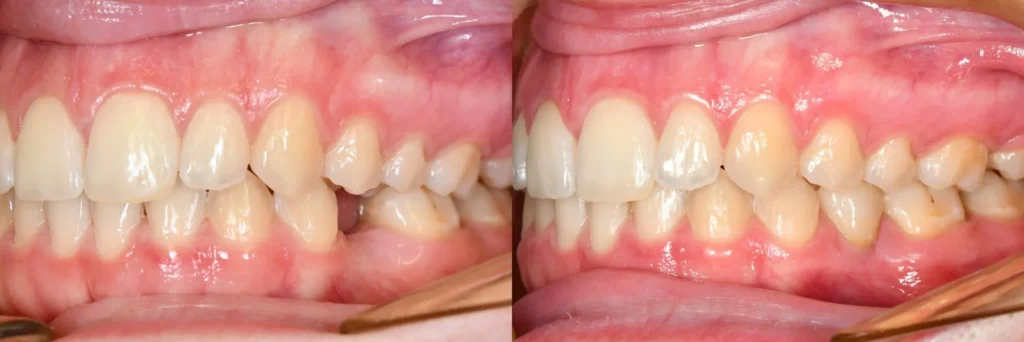

dentalni implantat prikaz slučaja

Kdo je primeren kandidat za zobne vsadke?

Večina pacientov so primerni kandidati,  vendar so potrebni nekateri pogoji:

• dobro oralno zdravje (brez parodontitisa ali aktivnih okužb),

• zadostna količina in kakovost kosti (ali možnost augmentacije),

• urejene kronične bolezni (sladkorna bolezen, osteoporoza),

• odsotnost škodljivih navad, kot je močno kajenje.

Če niste prepričani, ali ste primerni kandidat, je najbolje opraviti pregled – po diagnostiki vam bo zobozdravnik natančno povedal, ali je poseg primeren za vas.